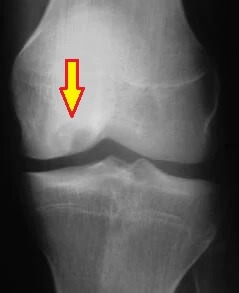

X-ray showing Osteochondritis Dissecans of the knee

1. X-rays: show changes in the bone and any loose fragments